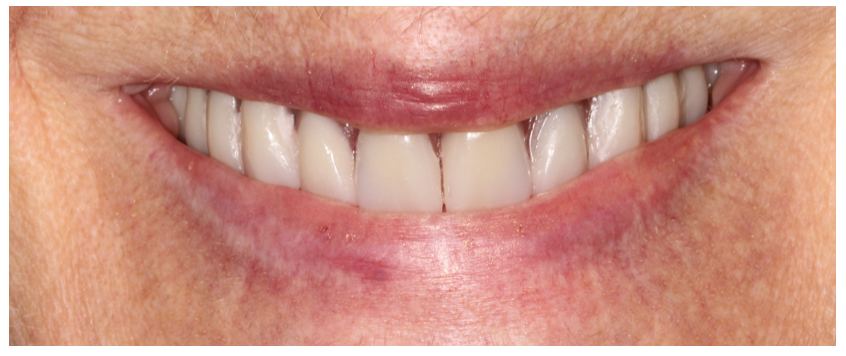

Aspects esthétiques à 4 mois :

Pour mémoire cas au départ :

Le point déterminant de la réussite esthétique de cette restauration a tenu au fait qu’au moment de la chirurgie initiale, la ligne de transition implanto-prothétique a été relevée au-delà de la ligne du sourire.